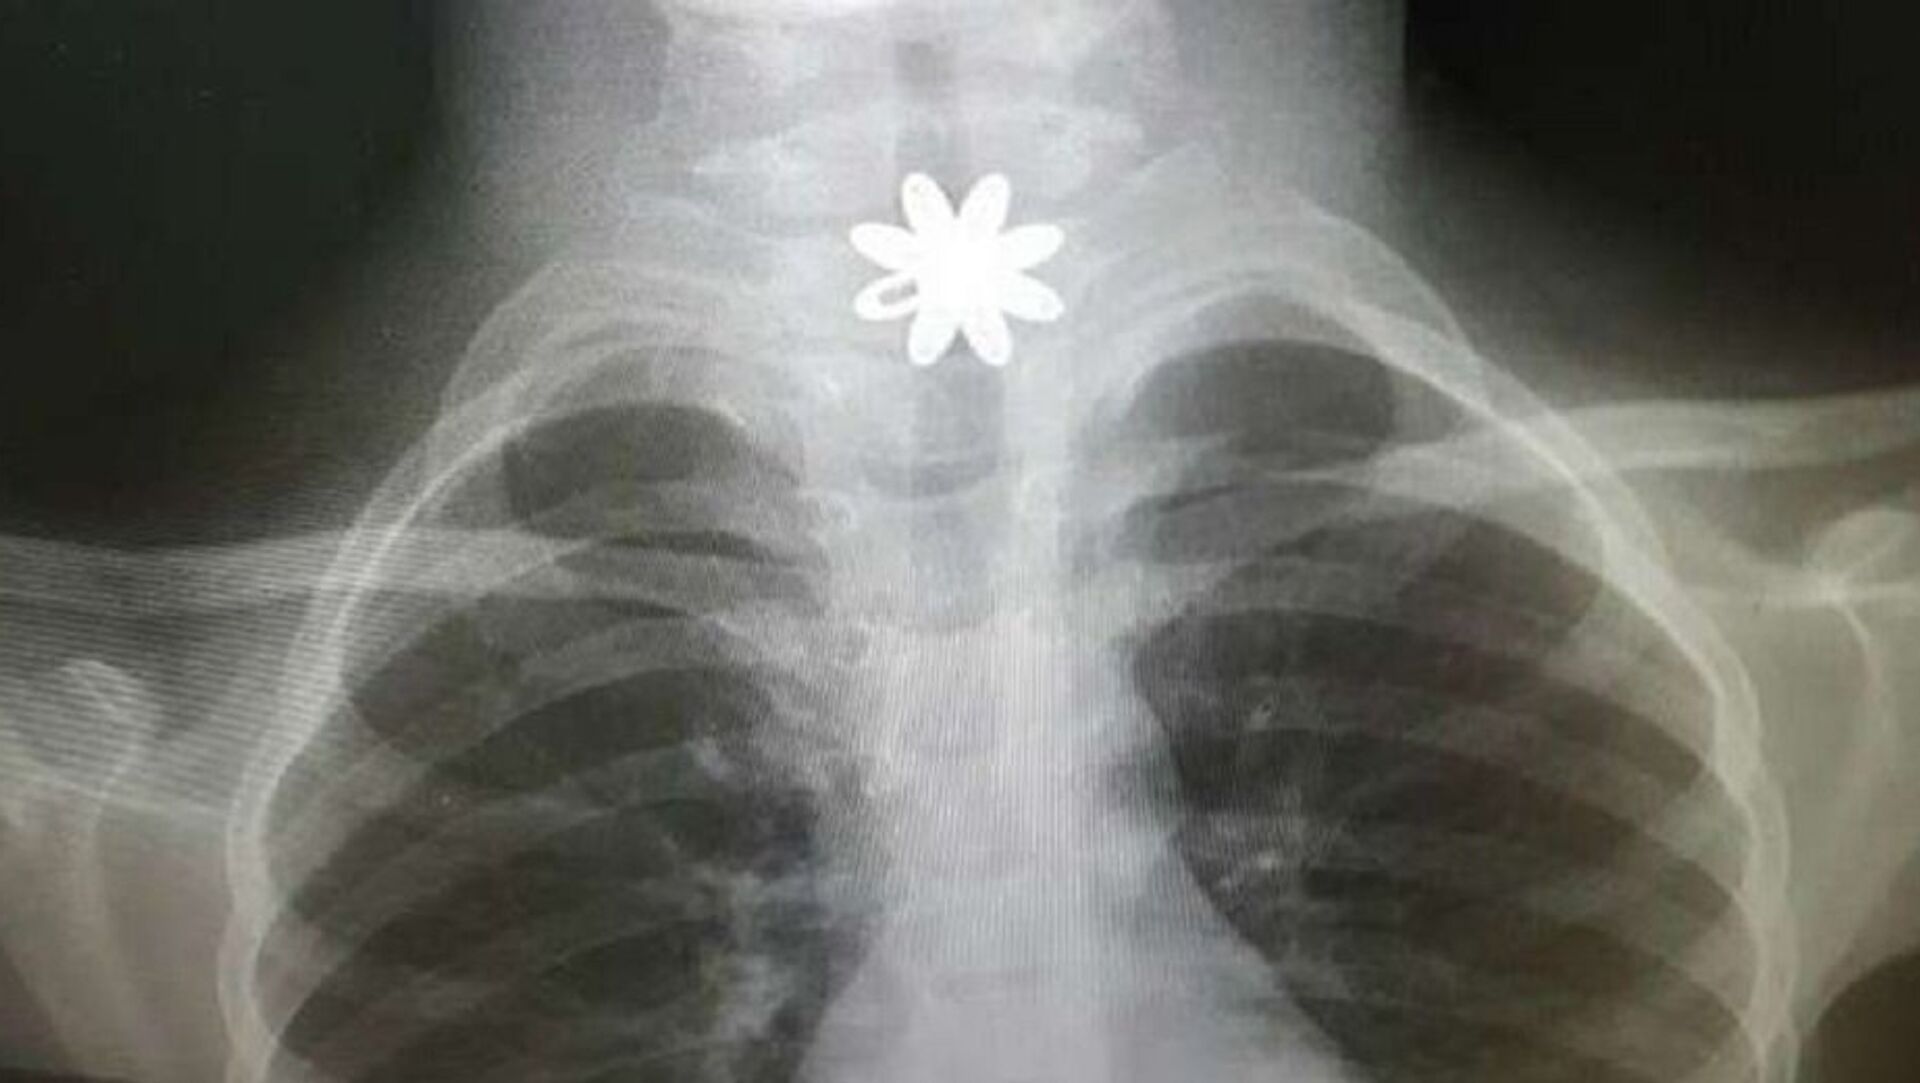

وفي التفاصيل، تم إدخال الطفلة إلى المستشفى وهي تعاني انسدادا في المريء، وبعد تشخيص الحالة، اتضح وجود قطعة معدنية حادة تشكل خطورة على حياة الطفلة، ممّا أدى إلى جروحٍ قطعية داخل المريء، بحسب "المواطن".

وخضعت الطفلة لعملية باستخدام منظار المريء الصلب، لاستخراج القطعة المعدنية، في وقت قياسي وبشكل دقيق وسريع، وتمّت معالجة الحالة، حيث غادرت المستشفى بصحةٍ جيدة.